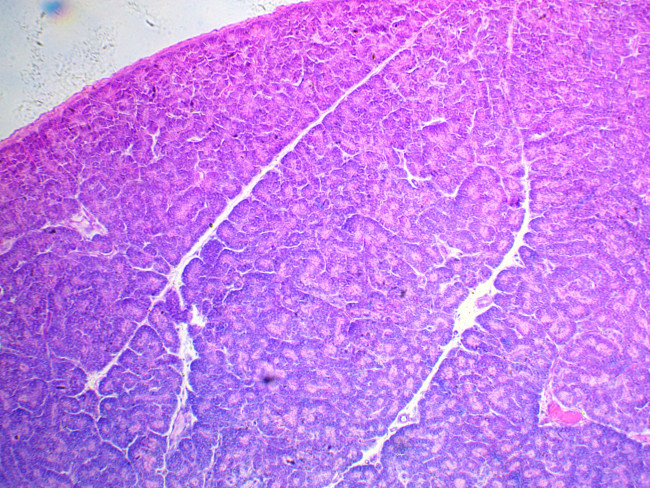

Камера ToupCam UCMOS05100KPA c сенсором Aptina MT9P006 представляет собой сенсор CMOS формата 1/2.5 дюйма, с количеством активных пикселей 2592 по горизонтали и 1944 по вертикали. Камера, благодаря однокристальной структуре, позволяет использовать оконный режим;возможности пропуска колонн и рядов и возможность получения мгновенного снимка предпросмотра (т.н. “snapshot”).

В камере используется технология обработки изображения Ultra-Fine Color Engine которая помимо использования процесса демозаики и настройки баланса белого включает в себя коррекцию “горячих пикселей” , конверсию цветового пространства, кросс-канальную коррекцию, коррекцию цветовых параметров, гамма коррекции и так далее.